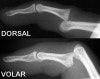

X-ray : 근위 지절간 관절 손상(PIP joint injury)